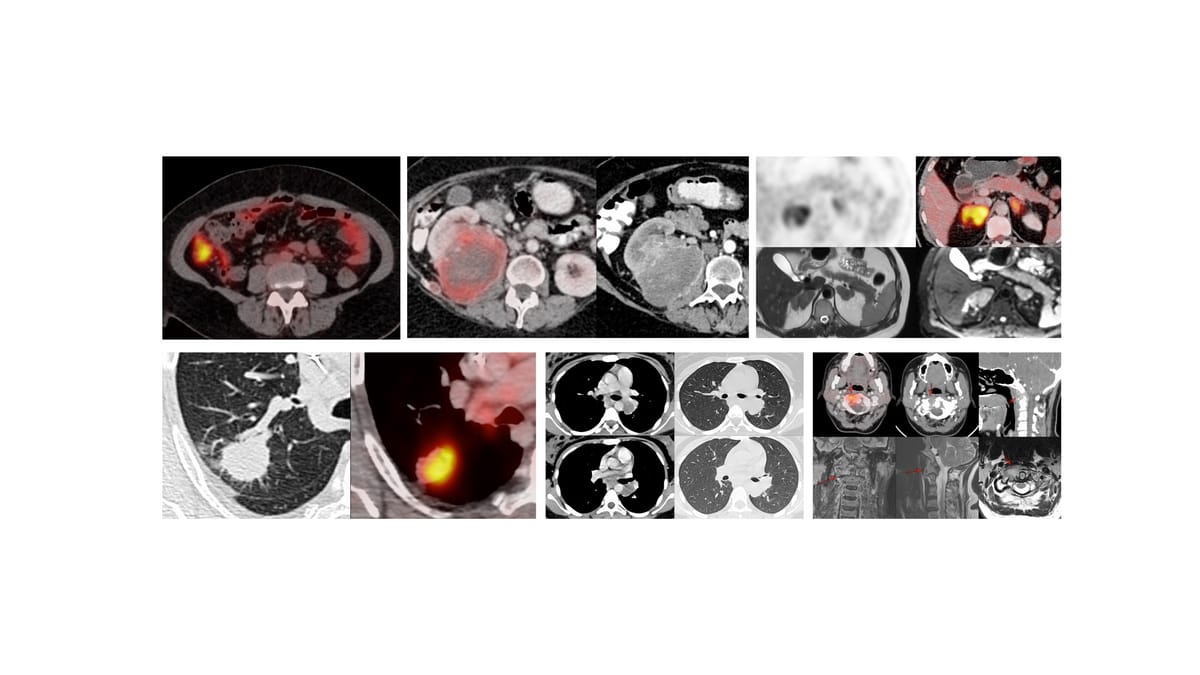

The Cases

Case 14: 24-years old with fever and a non-resolving right upper lobe mass-like consolidation

Case 15: 71-years old 40-plus pack years history smoker with non-resolving pleural effusion and an opacity in the right lower lobe

Case 16: 32-years old with fever, backache and an L4/5 lesion

Case 17: 56-years old treated for Ca esophagus had new retroperitoneal para-aortic nodes on PET

Case 18: 31-years old with chest pain and SVC syndrome